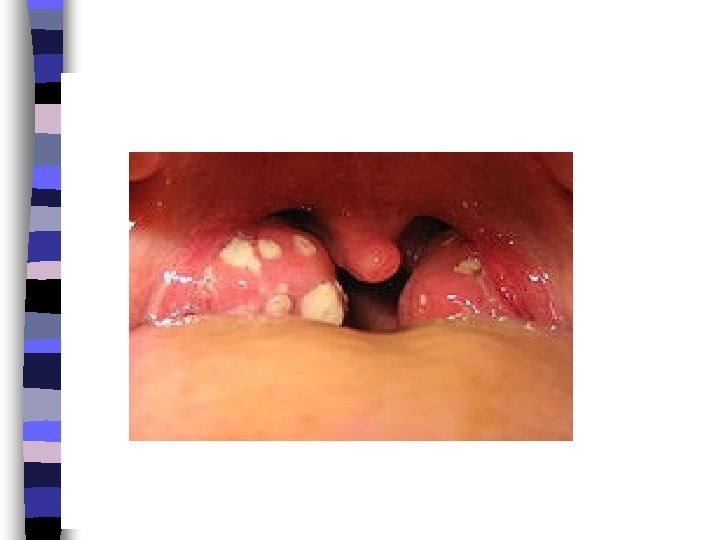

Tonsillitis is a swelling of the tonsils, which areas of lymphoid tissue on either side of the throat. Tonsils can become swollen when they are infected by bacteria or a virus. This is a common occurrence in children.

Symptoms of tonsillitis may include: n Ø Ø Ø Ø Sore throat. Difficult swallowing Fever. Headache. White patches in the throat or tonsils. Red, swollen tonsils. Pain when swallowing. Vomiting. Sore glands in the throat or jaw.

Chronic tonsillitis